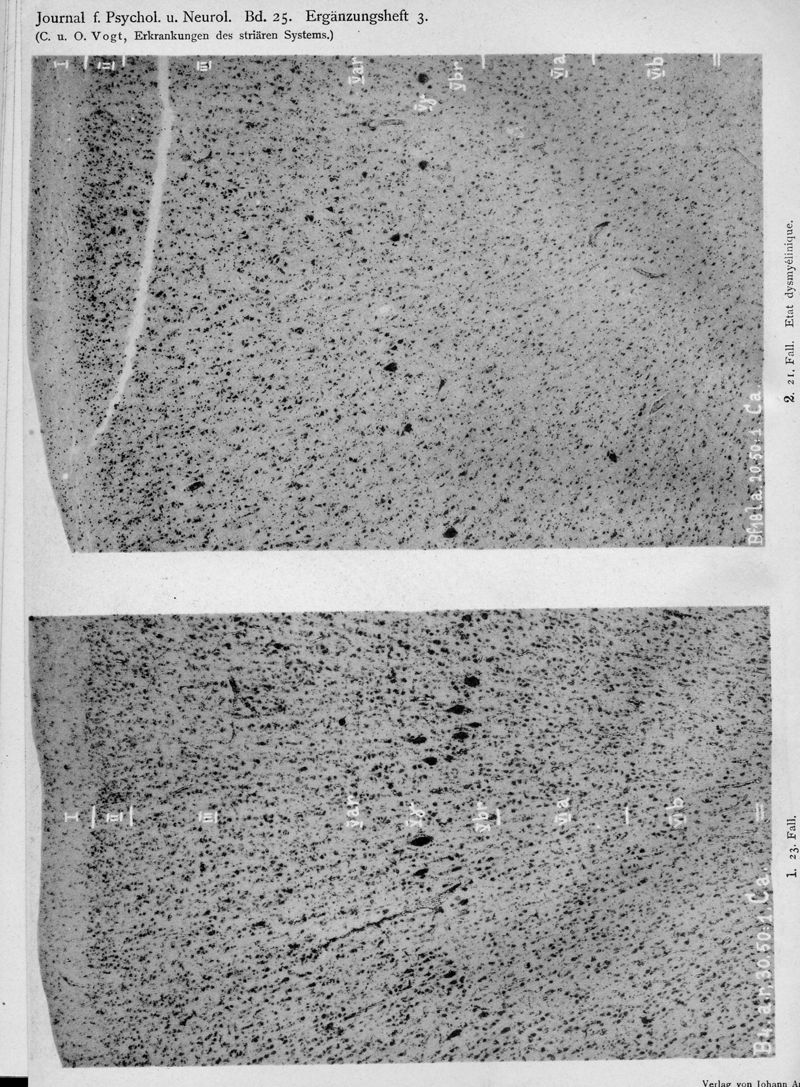

VOGT, Cécile / VOGT, O.

In : Journal für Psychologie und Neurologie,

1920, Vol. 25, pp. 627-846